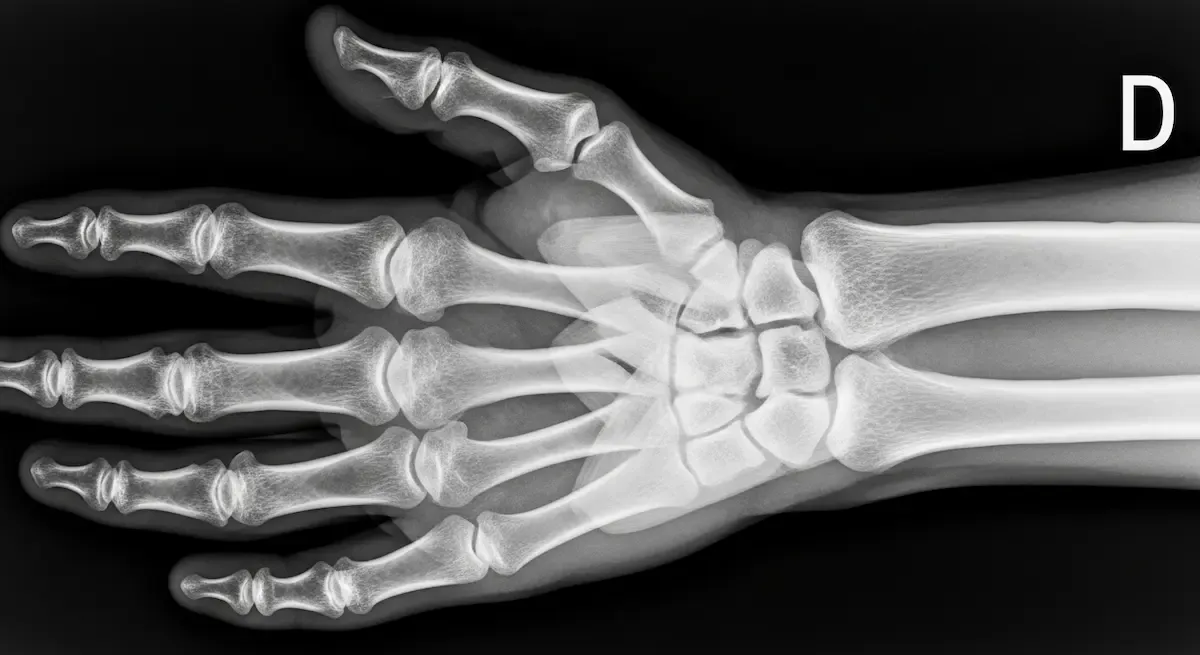

Ao longo da minha trajetória como ortopedista especializado em cirurgia da mão e punho, a bossa carpal é uma das condições mais frequentes que encontro em meu consultório. Esta protuberância no dorso do punho, tecnicamente conhecida como cisto...